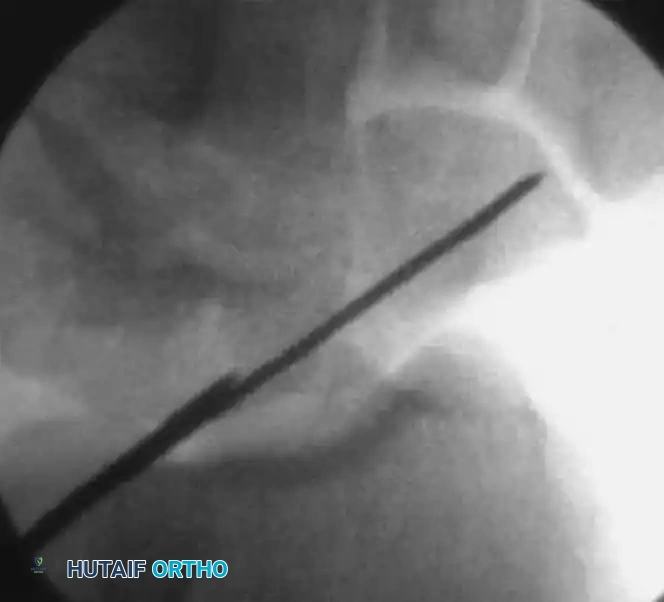

Guidewire Insertion A

Guidewire Insertion B

Guidewire Insertion C

FIGURE: (A, B) The guidewire is placed at the base of the proximal pole and driven along the central axis. (C) The wrist is extended, and fracture alignment alongside guidewire position is confirmed.

2. Incision and Guidewire Insertion

• Make a small (3-5 mm) skin incision at the marked location. Use a hemostat for blunt dissection down to the dorsal capsule of the wrist joint to protect the extensor tendons and terminal branches of the superficial radial nerve.

• Load a double-pointed 0.045-inch (1.14-mm) K-wire into a powered wire driver.

• Insertion: Under live fluoroscopic control, insert the wire starting at the exact center of the proximal pole (the center of the "ring").

• Pass the guidewire from dorsal to volar, directing it down the central axis of the scaphoid and out through the trapezium.

• Technical Tip: Use a 12-gauge angiocatheter over the K-wire to protect the dorsal soft tissues during insertion. Keep the wrist flexed during this step to prevent the guidewire from bending against the radius.